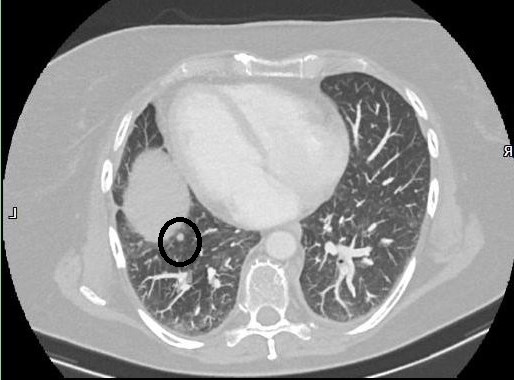

Ich habe schon einen beachtlichen Stapel voller CDs mit Bildern von allen möglichen meiner Körperteilen, aber erst jetzt bekomme ich das kleine Böse so gezeigt, dass ich es zu Hause auch wiederfinden kann. Die kleinere und einzige eindeutige Metastase ist hier zu sehen. Ziemlich genau in der horizontalen Mitte des Bildes am unteren linken Rand der Eiform, die aus dieser Sicht mitten im Lungenflügel gebettet scheint, aber nur schon den Beginn des Zwerchfells darstellt, sitzt diese winzig kleine runde Form. also hier:

Wenn ich meinen Blick endlich von dem kleinen tanzenden Figürchen abwenden kann, das da unten im linken Lungenflügel (also in Wirklichkeit im rechten, aber ich will jetzt mal nicht kleinlich sein) mit gesenktem Kopf herumgeistert, frappiert mich die Winzigkeit dieser Erbse, etwa 5 mm heißt es. Seine wohlgeformte Rundheit zeichnet es als eindeutige Metastase aus, im Gegensatz zu allen anderen Veränderungen, die, wie es mir bei Radiologen öfters passiert, nur schriftliche Metastasen sind, im trauten Gespräch eher nicht. Dieses eine Pünktchen ist also die Ursache all der neuerlichen Aufregung. Unscheinbar trifft es am besten. Es blinkt nicht grellrot auf, es pulsiert nicht, nix. Und es wächst nicht, das ist die gute Nachricht.

OH MY GOSH! (das sagt man an Stelle von „Oh my God“, wenn man aus der Kirche ausgetreten ist ;-)) Es ist natürlich von Bedeutung, dass diese Bilder seitenverkehrt sind. Natürlich spüre ich diese Stelle, ich weiß auch genau, wo sie sich befindet, nämlich dort, wo ich den Krebs lokalisieren würde, wenn ich mich nicht erst gedanklich auf die Reise des wo-war-das-jetzt-wieder-ach-ja-der-ursprungskrebs-sitzt-in-der-rechten-brust begebe, sondern einfach spontan auf die Stelle zeigen müsste, wo er sitzt:

Darf ich vorstellen: Meine Mitte, einmal durchgeschnitten, wie wenn die Fleischfachverkäuferin eine Scheibe Schinken abschneidet. Das ist das Zentrum der Zerstörung, dort suppten die anderthalb Liter Pleurawasser vor sich hin, dort saß die schlimmste aller Entzündungen vom gruseligen Drainage-Schlauch. Klar. Und jetzt sehe ich auch, wie das kleine tanzende Figürchen sich dorthin neigt. Klasse, da ist das Thema fürs nächste Aquarell.